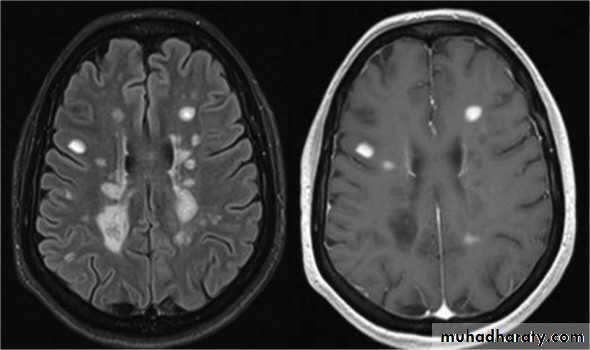

MRI :characteristic abnormalities are found in >95% of patients, although more than 90% of the lesions visualized by MRI are asymptomatic

Lesions are frequently oriented perpendicular to the ventricular surface,(Dawson’s fingers)

Lesions larger than 6 mm located in the corpus callosum, periventricular white matter, brainstem, cerebellum, or spinal cord are particularly helpful diagnostically

MRI shows multiple high-signal areas in a pattern similar to that of MS, although often with large confluent areas of abnormality. The CSF may be normal or show an increase in protein and lymphocytes (usually 200 cells/L) . The clinical picture may be very similar to a first relapse of MS.